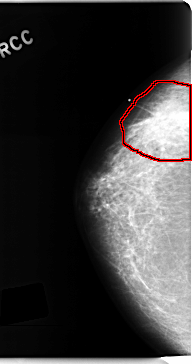

C_0201_1.RIGHT_CC

RIGHT_CC LINES 4728 PIXELS_PER_LINE 2488 BITS_PER_PIXEL 12 RESOLUTION 50 OVERLAY

FILE: C_0201_1.RIGHT_CC.OVERLAY

TOTAL_ABNORMALITIES 1

ABNORMALITY 1

LESION_TYPE MASS SHAPE IRREGULAR MARGINS SPICULATED

ASSESSMENT 5

SUBTLETY 5

PATHOLOGY MALIGNANT

TOTAL_OUTLINES 1

BOUNDARY